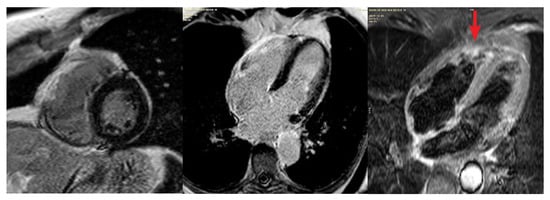

On the third day of admission, cardiac magnetic resonance imaging (CMR) was performed and revealed an isolated transmural scar of the right ventricular free wall with surrounding myocardial edema on T2-weighted images. Accordingly, the diagnosis of iRVMI was established (Figure 4).

Figure 4. T1 magnetic resonance imaging (MRI) scan showing late gadolinium enhancement of the lateral right ventricular wall (scar, impaired microcirculation). The T2 MRI scan shows edema of the lateral right ventricular wall (acute myocardial infarction, red arrow).